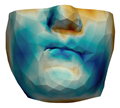

| M1 |  |  |  |  |  |  |

| M2 |  |  |  |  |  | |

| M3 |  |  |  |  |  | |

| M4 |  |  |  |  |  | |

| M5 |  |  |  |  |  |

| M6 |  |  |  |  |  |  |

| M7 |  |  |  |  |  | |

| M8 |  |  |  |  |  | |

| M9 |  |  |  |  |  | |

| M10 |  |  |  |  |  |